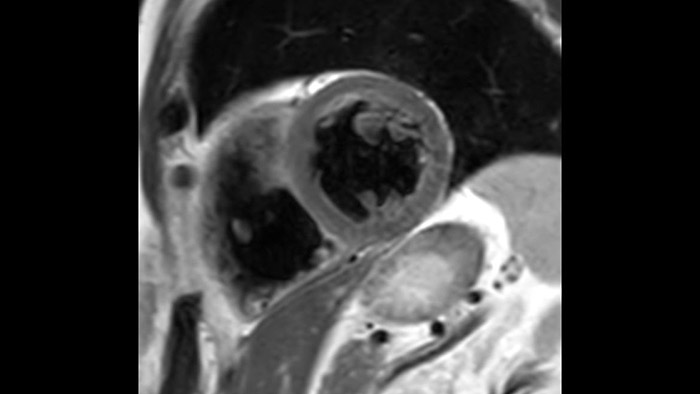

Os diagnósticos tradicionais não têm a visibilidade necessária para ver os efeitos do tratamento cardíaco ou para detetar disfunção antes que os sintomas ocorram. Ao combinar a sequência de aquisição de RM da Philips Fast-SENC com a ferramenta de análise MyoStrain da Myocardial Solutions, as alterações precoces e subtis da função cardíaca podem ser medidas diretamente.

A utilidade do diagnóstico e prognóstico da RM cardíaca está a aumentar. Avalie a anatomia e função do coração utilizando aquisições cine, adquira informações sobre a perfusão e viabilidade do tecido cardíaco, visualize potenciais edemas com sequência de sangue escuro, aceda e quantifique mesmo a caracterização do tecido com a CardiacQuant.

O IntelliSpace Portal MR Caas7,8 Strain9 ajuda no diagnóstico e monitorização do paciente ao proporcionar parâmetros globais de deformação, tais como deformação longitudinal global (GLS), deformação circunferencial global (GCS) e deformação radial global (GRS), utilizando imagens de RM de eixo curto e longo, bem como descrevendo a deformação do miocárdio, como encurtamento, espessamento e alongamento durante o ciclo cardíaco.